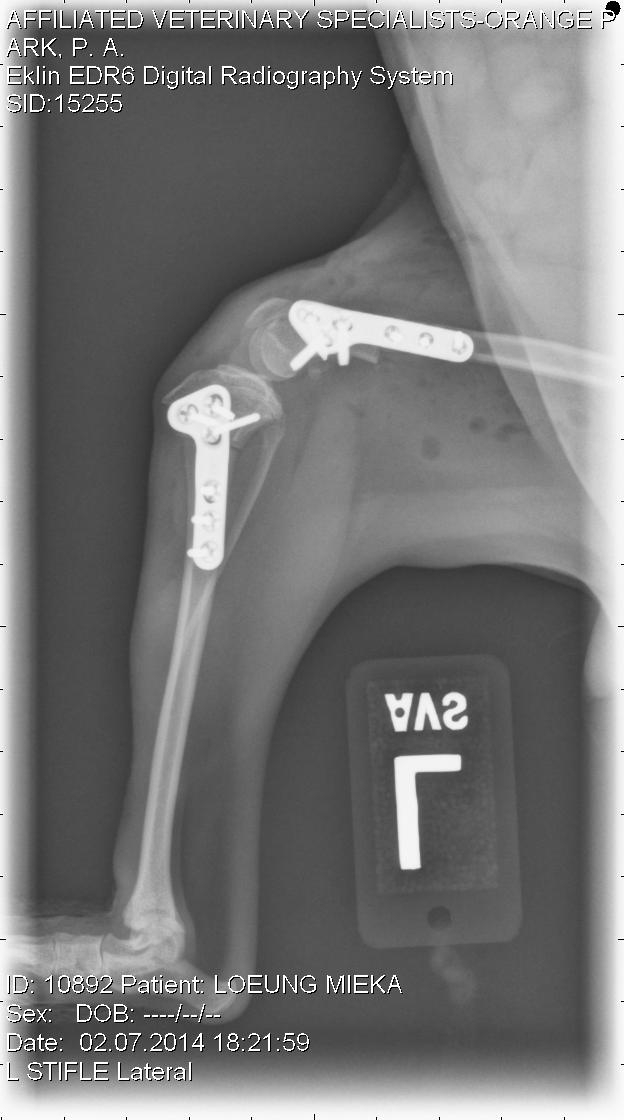

Not to bore with all the details of surgery, but four surgeries were planned for Mieka. We decided to start with the left side, however both were bad. We corrected the alignment in her knee by correcting the deformities in the tibia and the femur and then secured the patella. In order to correct the alignment, we had to cut the bones (tibia and femur) and adjusted with a plate and screws. Once she began to heal from that surgery, we addressed the hip by performing a femoral head ostectomy (removal of the femoral head).

Note the more normal appearance of the tibia, femur and patella.